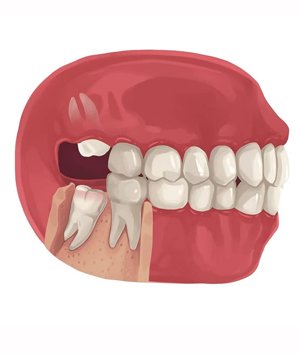

• If a wisdom tooth doesn’t have room to grow, results in pain, food entrapment, infection or gum disease, tooth decay infection or other dental problems, you’ll likely need to have it pulled.

• Damaging the nearby tooth and while straightening other teeth (orthodontic treatment).